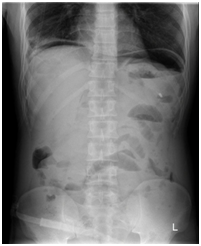

X-ray erect abdomen and chest x ray revealed air under diaphragm (Figure1-2) .He underwent lab tests , which showed normal total leukocyte count (8.67x10^3/µl), nevertheless his coagulation profile (prothrombin time: 20.2 INR: 1.85) was deranged suggestive of sepsis, peritoneal fluid(intraoperative) sent for culture and sensitivity was sterile.

Figure 1 X ray erect abdomen.